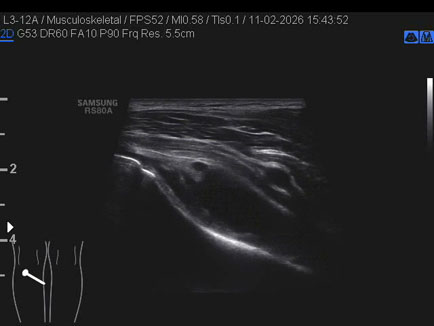

Ecografia del: 11/02/2026

Strumento: Samsung

Sonda: Lineare

Commento all'esame: rottura giunzionale muscolo-tendinea del popliteo.

Conclusioni: rottura miotendinea del muscolo popliteo sinistro (myotendinous tear of the left popliteus muscle).

Realizzazione: Dr. F. Pietro Tarini - Gubbio (PG)